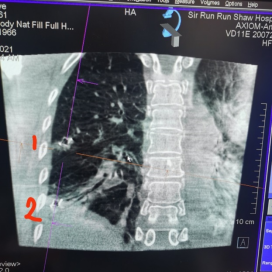

手术前,先利用高精度薄层胸部CT进行三维重建规划,计算好导航气管镜进入的路径。

手术中,在虚拟导航气管镜引导下,气管镜顺利达到病灶附近预设的目标。

到达目标位置后,将H-Marker置入器直接置入气管镜的工作孔道,非常方便地将H-Marker放置在需要定标的位置上。

为保障万无一失,释放H-Marker前后,导航团队均利用高大上的锥形束CT进行术中实时确认。